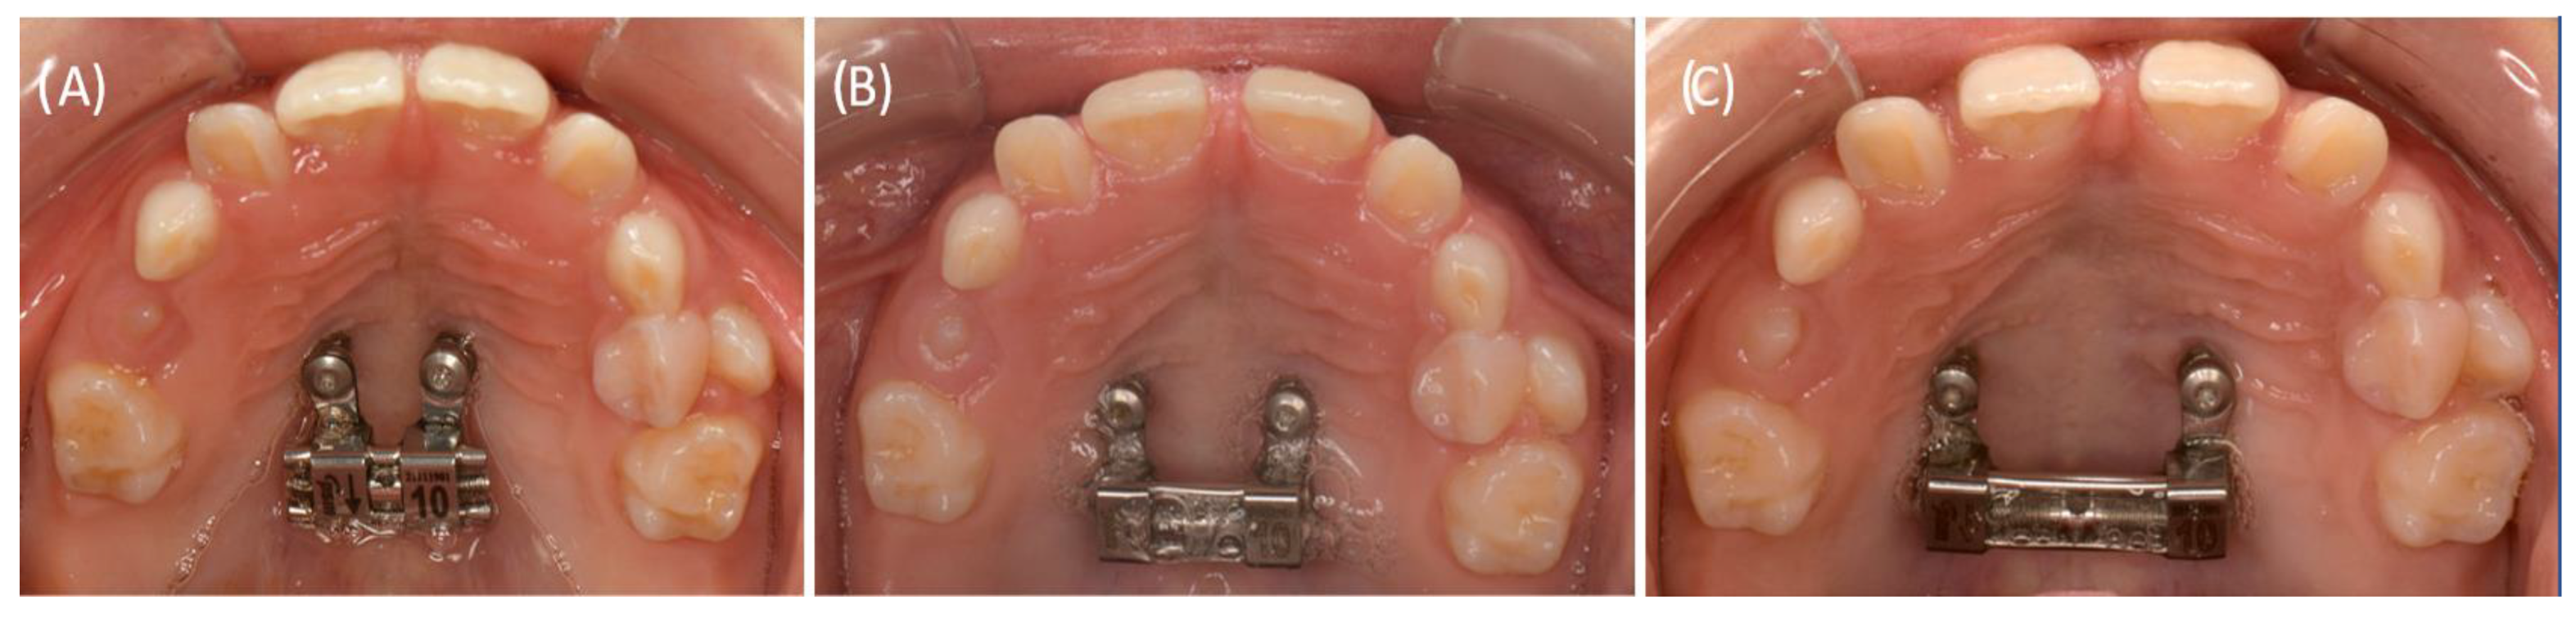

2.4.2. RPE Using the Skeletal-Anchorage Hyrax Appliance

2.4.3. Alignment of the Surgically Exposed Teeth by Using Skeletal Anchorage